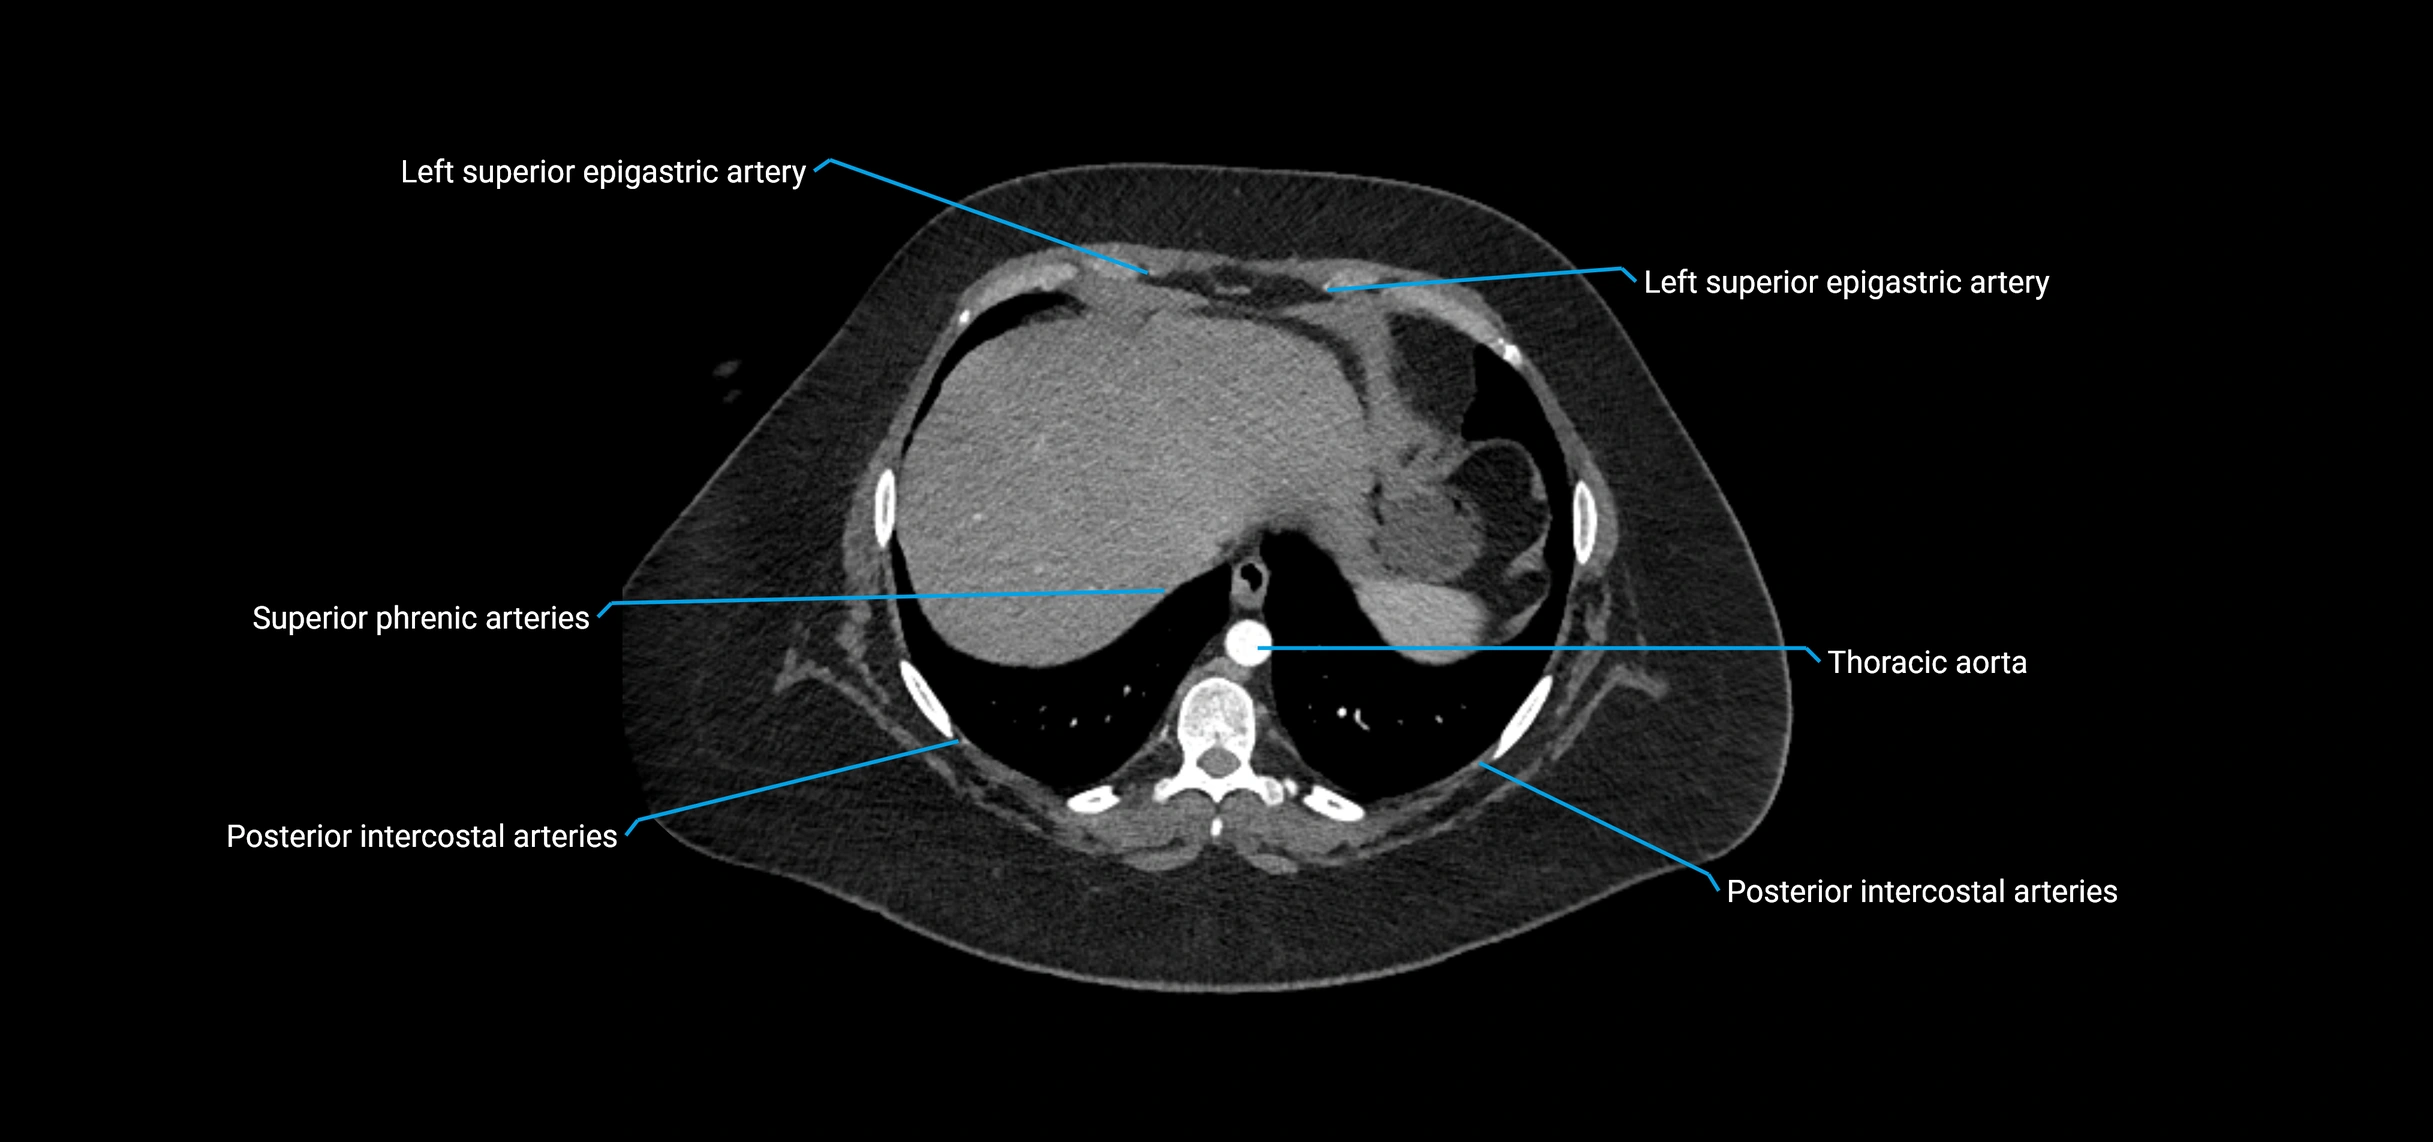

CT Appearance

Non-contrast CT:

• Appears as a tubular soft tissue structure anterior to vertebral bodies

• Calcified atherosclerotic plaques appear as hyperdense foci along the wall

• Useful for screening abdominal aortic aneurysm (AAA) size and mural calcification